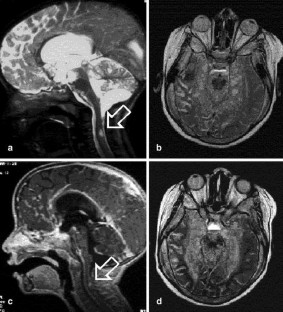

Fig. 2.